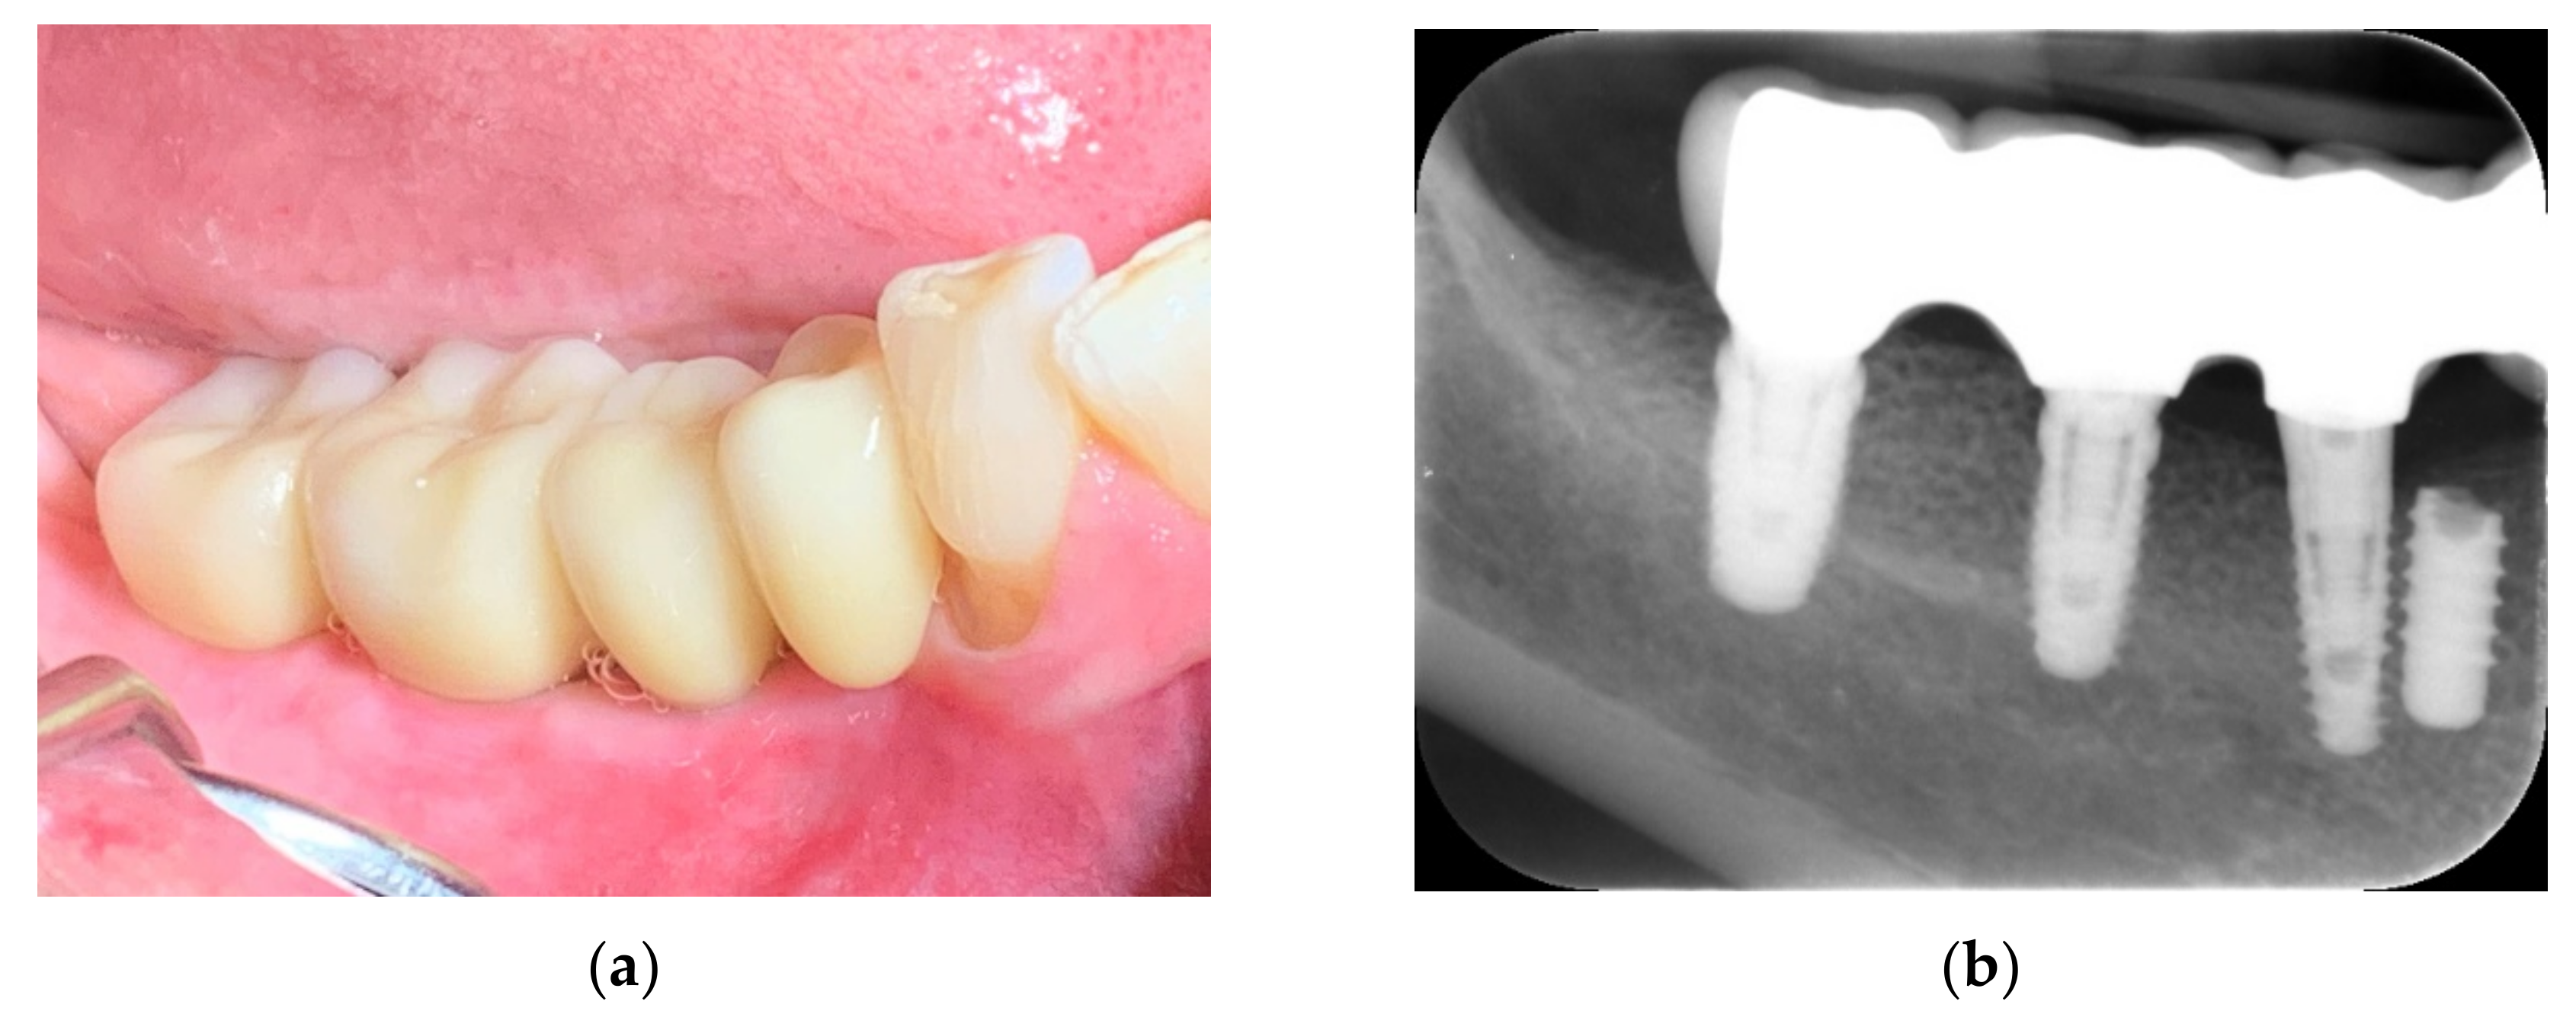

Impressions were taken using an open impression tray. The abutments were individually designed, and the bridge was made with a zirconia structure and baked porcelain for a screw-retained cantilever bridge. The bridge was delivered and screwed on at 30–35 Ncm 4 months after implant placement (Figure 19a–c) and, in total, ten months after placement of the allograft customized bone block, showing an excellent esthetic result. Teflon tape was placed over the screws to establish retrievability. The Teflon was covered finally with a composite to improve the esthetic clinical outcome (Figure 20a,b).

Figure 19.

Prosthetic planning and design (a–c).

Figure 20.

Bridge delivery (a) and control radiograph (b).

10. Follow-Up

After 15 months, the patient returned to the practice for a regular check-up. The soft tissues presented a healthy condition and pink color (Figure 21a), with excellent plaque control. The postoperative radiograph showed bone remodeling at the distal side of tooth #30 (Figure 21b).

Figure 21.

Follow-up at 15 months: clinical view (a) and control radiograph (b).